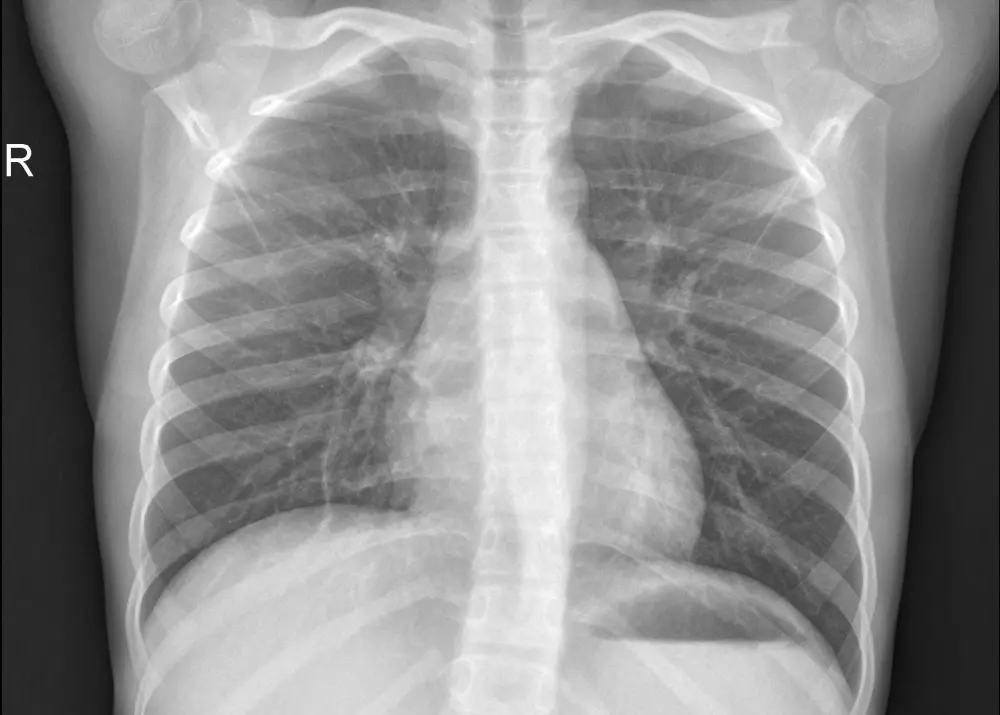

نموذج ذكاء اصطناعي باستخدام تقنيات Deep Learning لتحليل صور الأشعة الصدرية (Chest X-Ray) واكتشاف الإصابة بالالتهاب الرئوي (Pneumonia). المشروع يعتمد على شبكة CNN مدربة لتحليل الصور الطبية بدقة، مع توفير واجهة ويب بسيطة باستخدام Flask لرفع صورة الأشعة والحصول على النتيجة مباشرة. ما ستحصل عليه: * كود المشروع كامل بلغة Python * نموذج الذكاء الاصطناعي المدرب * تطبيق Flask لتحليل الصور * شرح طريقة تشغيل المشروع